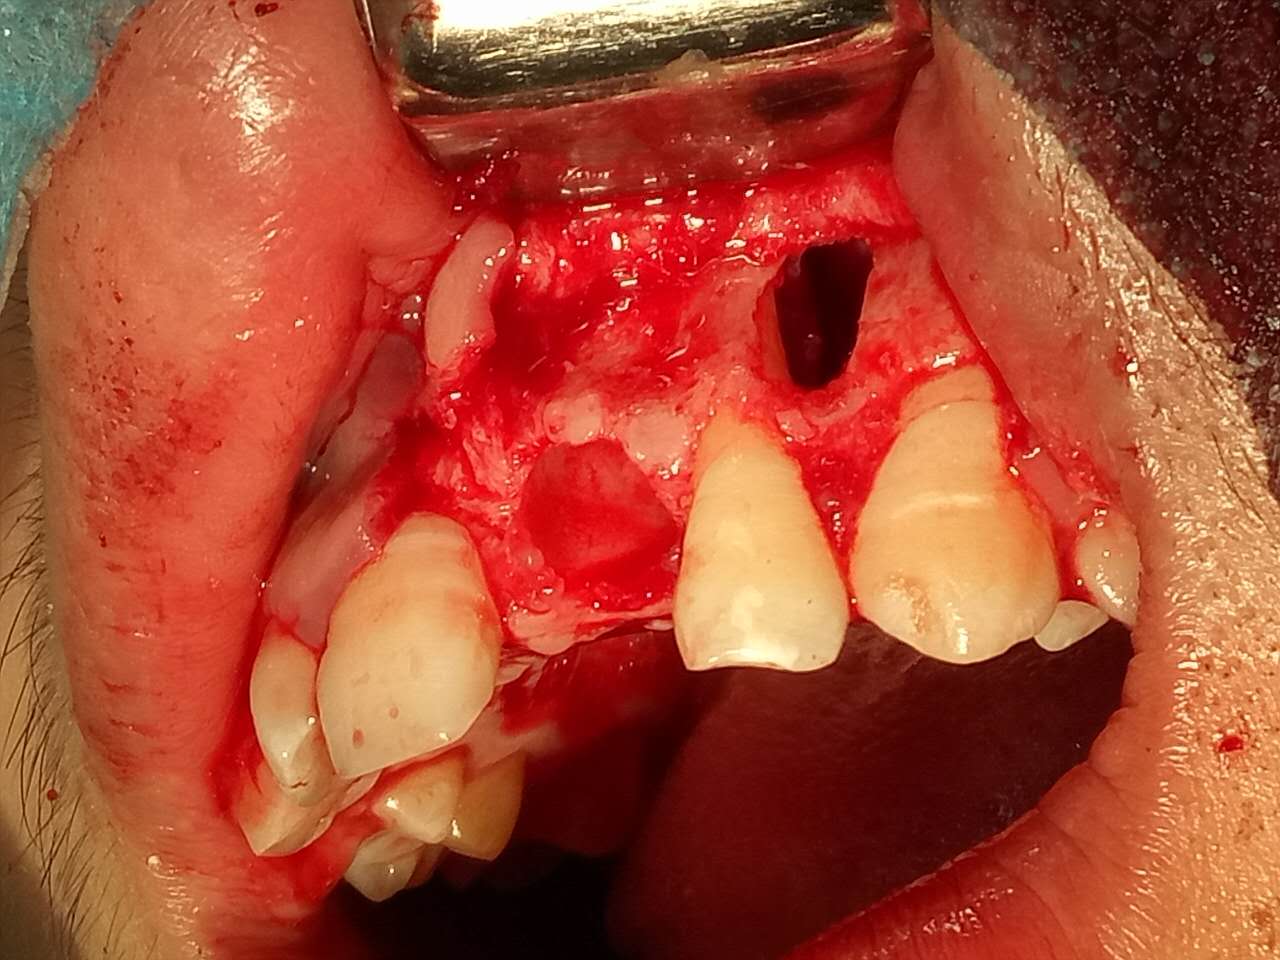

死髓牙2度,沒保留價(jià)值了,外傷造成的外吸收,即使到充也容易出問題。和患者溝通,要求做種植,用了兩個(gè)骨膠原,側(cè)切、尖牙沒事,側(cè)切做了一次根充